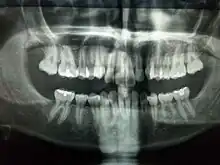

Galería de imágenes